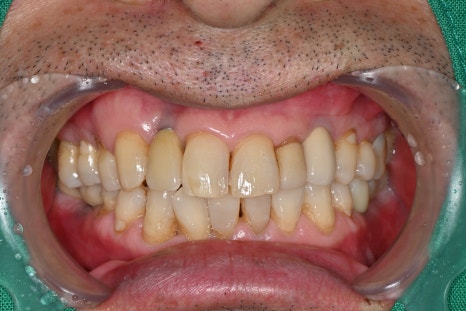

보철 제작과 최종 장착

마지막 단계에서는

환자의 교합에 맞는 보철물을 제작하여 장착합니다.

어금니 임플란트는 씹는 힘을

견뎌야 하기 때문에 정확한

교합 조정이 매우 중요합니다.

임플란트 치과에서는

교합을 여러 번 확인하며 미세 조정을 진행합니다.

치료 후 변화

임플란트는 단순한 치료가 아니라

삶의 질을 회복하는 시술입니다.

치료 후 환자분은

어금니로 음식을 편하게 씹을 수 있게 되었으며,

저작 기능 회복

통증 감소

잇몸 상태 안정

일상생활 개선

등의 변화를 경험하셨습니다.